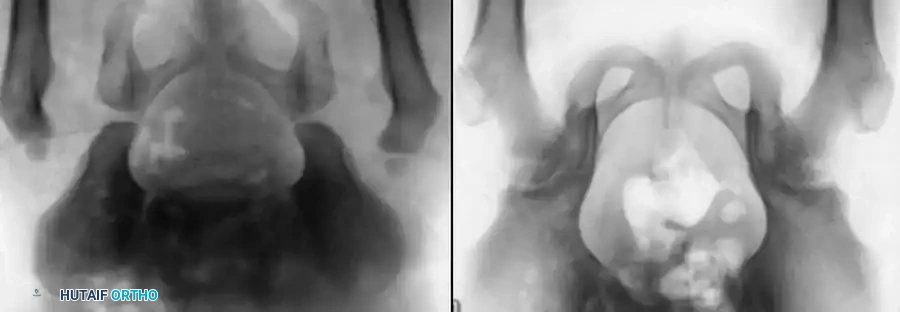

Radiographic evaluation: Normal hip anatomy (left) versus Dysplastic hip anatomy (right) demonstrating disruption of Shenton's line and an increased acetabular index.